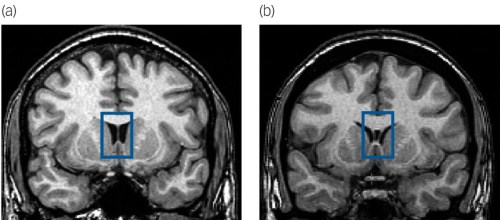

“Illustration of normal septum pellucidum (thin membrane separating the lateral ventricles) in a non-antisocial control (a) and the cavum septum pellucidum in an individual with antisocial personality disorder (b).

Coronal magnetic resonance image slices are at the level of the head of the anterior limb of the internal capsule, caudate, putamen, accumbens, and insula. Highlighted within the bue box is the septum pellucidum, dividing the lateral ventricles and bordered superiorly by the body of the corpus callosum and inferiorly by the fornix. The normal control (a) shows a fused septum pellucidum, whereas the participant with antisocial personality disorder (b) shows a fluid-filled cavum inside the two leaflets of the septum pellucidum.”